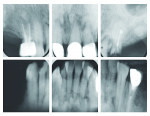

A female African American patient was diagnosed with PCOD based on the information in her radiographs. Associated teeth were tested and found vital and the patient presented with ill-fitting partials and root tips. Her chief complaint was pain while chewing and discomfort from the partials. Radiographically, the mixed lesions were seen in all four quadrants of her jaws, and were associated with the teeth that were present and those that were previously extracted (Figure 1).

The patient’s clinical presentation of edentulism and the subsequent use of partial dentures resulted in severe bone atrophy posteriorly (Figure 2 through Figure 5). The patient’s indecision regarding her future dental care led to broken crowns that were cemented daily with the partials until the pain led to a decision for definitive treatment.